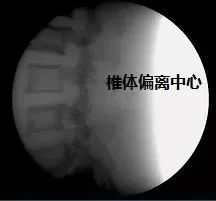

3. 透视的部位对准增强器中心:如果不对准中心,有可能导致成像偏黑甚至出现废片,特别是拍脊柱图像时,正位时比较容易对准,但是侧位时要注意,预想一下椎体位置,保证人体覆盖了至少在 50%~70% 左右的中心位置。

某机器的脊柱正位,侧位正常片,侧位偏离中心后偏暗图像以及和侧位严重偏离中心后导致的废片。注意使用的是体模,和真实人体 X 光片有一定的差别。